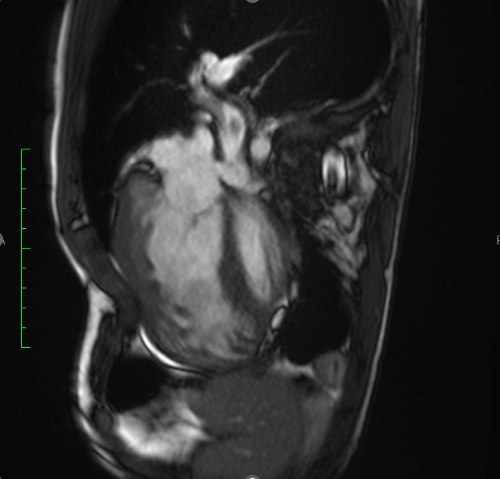

We describe a case of a male patient with left-sided CDH diagnosed prenatally and surgically repaired in the neonatal period. He developed severe PH requiring extracorporeal membrane oxygenation (ECMO), prostaglandins, and prolonged dual therapy with endothelin receptor antagonists (bosentan, macitentan). He was weaned off oxygen at age 3 but required re-initiation at 17 due to progressive desaturation. Additional congenital anomalies included repaired aortic coarctation and multiple abdominal surgeries. At age 20, clinical deterioration followed the introduction of selexipag, with worsening hypoxemia, increased oxygen requirements, and suspicion of pulmonary vascular disease progression. Cardiac catheterization and cross-sectional imaging were attempted but were limited by profound hypoxemia and instability.

Descriptive findings revealed resting oxygen saturations of 82–85% on 4 L/min supplemental oxygen, WHO functional class III, and echocardiographic signs of right ventricular overload. Laboratory markers showed elevated NT-proBNP (1,347 pg/mL). No evidence of acute thromboembolism was found. Clinical worsening was temporally associated with selexipag initiation. Drug withdrawal led to partial functional and oxygenation recovery. Based on clinical trajectory and ancillary testing, Group 3 PH secondary to developmental lung disease was the working diagnosis. The case was discussed at a national PH board, confirming the suspicion of irreversible pulmonary vascular compromise.